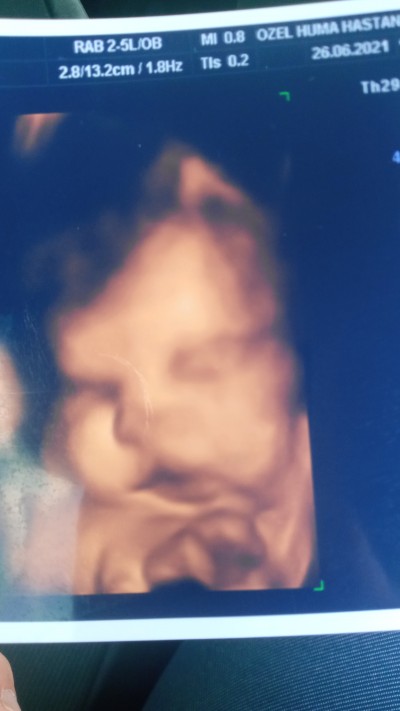

32+5 haftalık gebeyim, dün doktor renkli ultrason resmi verdi o an hastanede bakmadım eve gelince bebişimize baktık yarık dudak gibi bir görüntü dikkatimi çekti, 23 haftalıkken ayrıntılı ultrasona girdim orada böyle bir şey söylememişti doktor, dünkü doktor da bir şey demedi, belki de inceleyerek bakmadı, acaba bu benim kuruntum mu?

image

Gebelik haftası 32+5

Oyyy maşallah ball dudaklı ya yaa yerimm öyle olsa doktor söylerdi kuzum ya

Maşallah kuzuya ♥️ bence öyle değil,köfte dudak :) bide sanki elinin üzerine yatmış, yatma pozisyonundan öyle çıkmış bence.Sağlıkla kavuşursunuz inşallah

Kalın dudaklı üst dudağı da kalkık maşallah:)

Yarık dudak değil yarık damak olur o da bı anomalidir öyle olsa doktor mutlaka söylerdi orda yanağını dayadı heralde o yüzden dudağı buzulmus :)

Hayır bence bal dudak olduğu için yan duruyor kafası hani bebislerin yanaklarını sikarsinda dudağı olur ya o şekilde duruyor

Kız ne yarık dudağı köfte dudak bu resmen maşallah :)